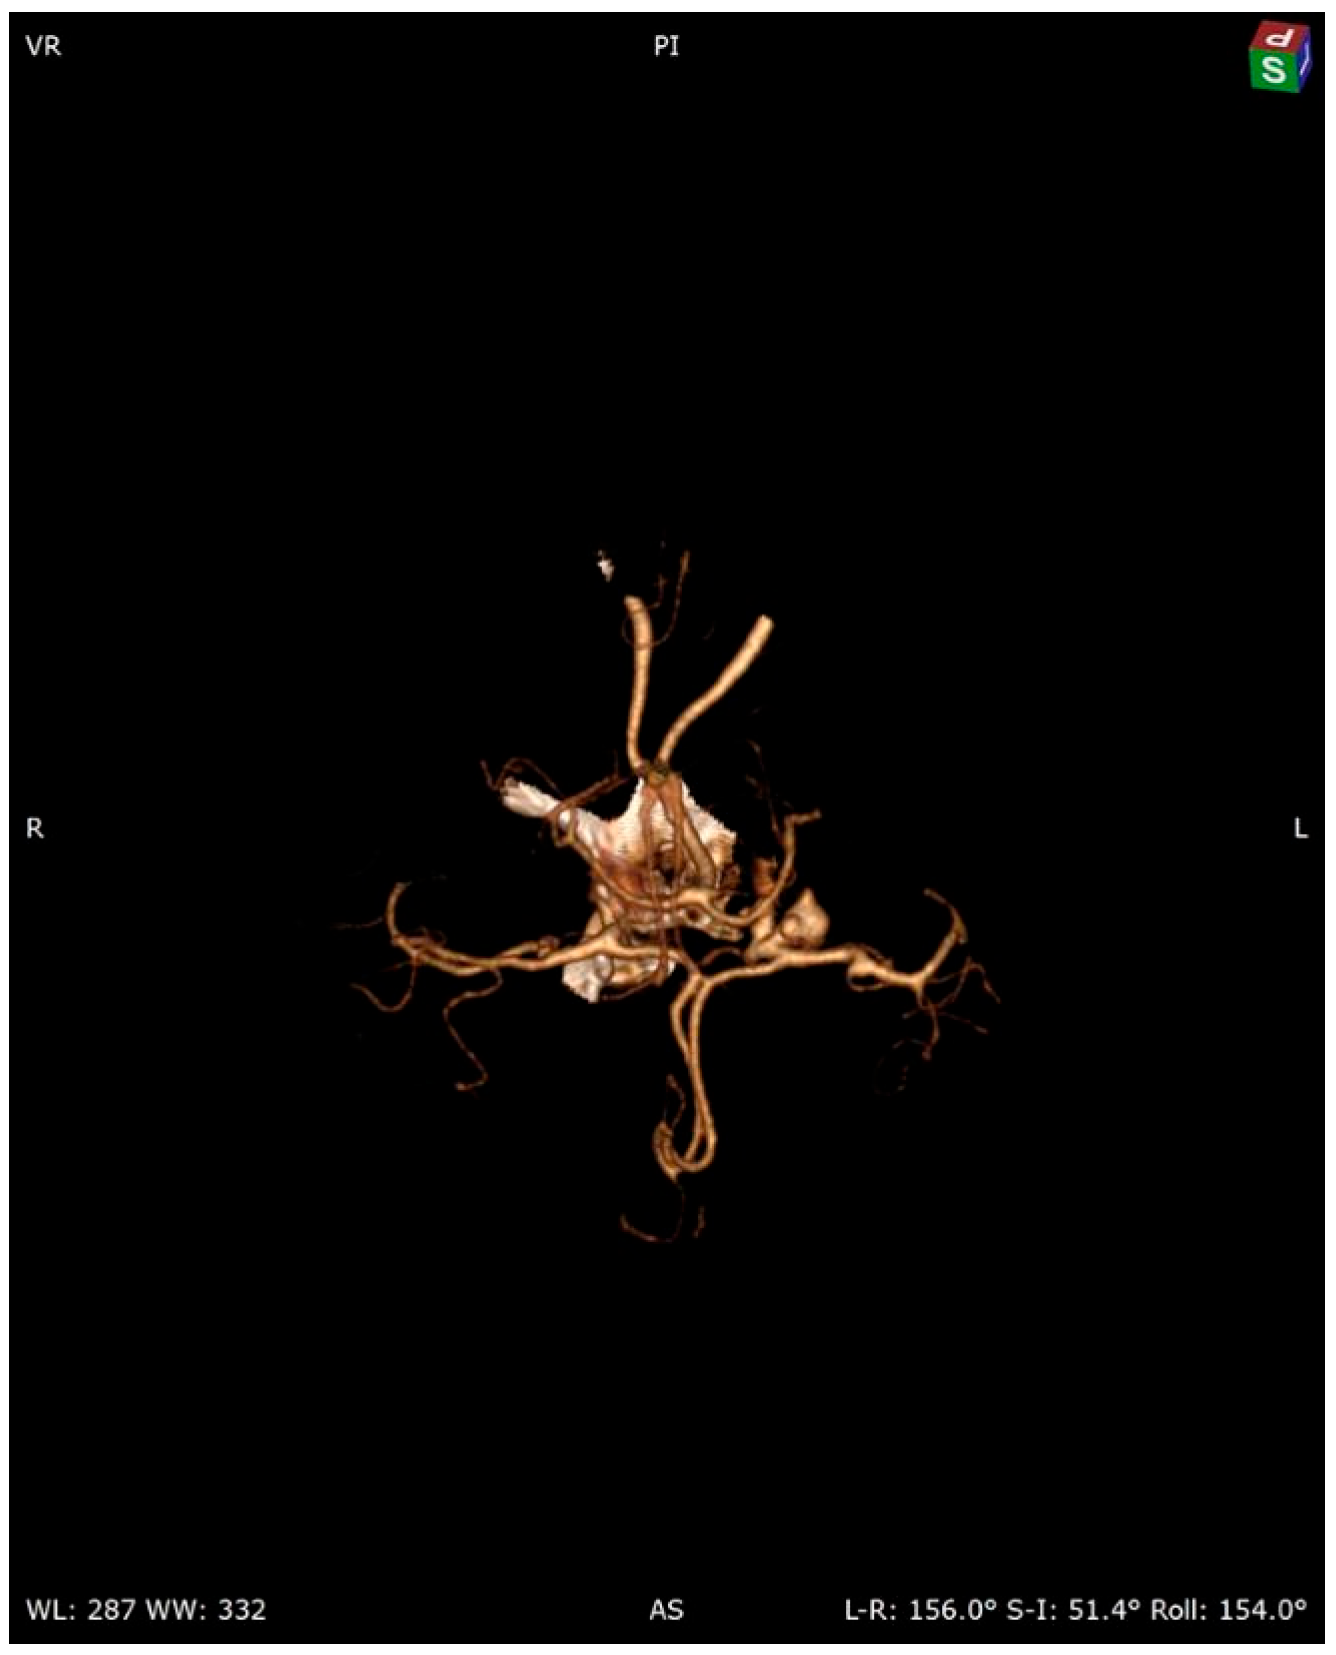

A 58-year-old woman treated for exudative pericarditis (effusion up to 6 mm) for the last 6 months was referred to a hepatologist/infectious diseases specialist with hypoechoic unclear lesions in the liver due to suspected hepatic tumor. Computed tomography confirmed simple hepatic cysts, while blood analysis revealed significant eosinophilia (23.4% in percentage, normal range 1–6%; eosinophil count: 1.45 in thousand eosinophils per microliter (K/μL), normal range 0.02–0.5 K/μL). The patient denied any symptoms, such as fever, abdominal pain, weight loss, cough or diarrhea in recent months; however, she described left-sided subjective eyeball enlargement, pain and redness. Her history included travels to Mexico, Egypt and Tunisia, as well as occasional raw meat consumption in Poland. She also had a dog, which did not receive regular parasite screenings and preventive medications. Her father had died from liver cancer. Lab tests confirmed the presence of IgG antibodies against Toxocara canis and sustained eosinophilia (18.1% in percentage, normal range 1–6%; eosinophil count: 1.01 in thousand eosinophils per microliter (K/μL), normal range 0.04–0.4 K/μL). Echinococcosis was excluded based on negative serology. Diagnosis of toxocariasis was further supported by clinical manifestations and exposure history with positive serology, and the patient was treated with mebendazole (200 mg twice a day for 5 days). Due to the suspicion of an ocular parasitic invasion, she was sent for an ophthalmological consultation. The ophthalmological examination was inconclusive, but head MRI revealed vascular abnormalities in brain arteries. CT angiography confirmed four aneurysms with one causing the constriction of an artery supplying the left eyeball (Figure 1, Figure 2 and Figure 3): two cerebral aneurysms of LICA (left internal carotid artery) size: 4.2 × 8.7 × 3.5 mm and 9.8 × 7.8 × 10.7 mm, one cerebral aneurysm of LMCA (left middle cerebral artery) size: 3.5 × 3.3 × 3.2 mm and the fourth enlargement for differentiation between an aneurysm and an infundibular dilations (3 mm) of LMCA. Clipping the aneurysms dissolved the ophthalmological problems. During the last check-up, normalization of the eosinophil count, full resolution of the ocular symptoms and no pericardial effusion were seen, further supporting our diagnosis of visceral toxocariasis. Hepatic cysts began to disappear. The patient was recommended to perform an abdominal ultrasound every 6 months.

Figure 1.

Cerebral 3D CT angiography.